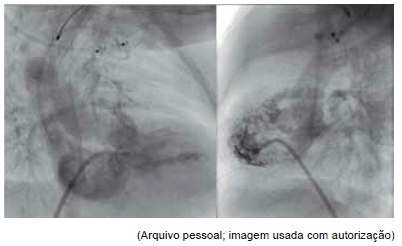

Observe as seguintes figuras de cateterismo cardíaco para responder à questão.

Com relação às figuras, o diagnóstico mais provável da cardiopatia congênita é:

As seguintes figuras de cateterismo cardíaco dizem respeito ao procedimento percutâneo: colocação de